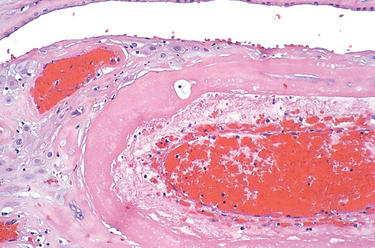

The placenta is composed of chorionic villi (Fig. 22-51) that sprout from the chorion to provide a large contact area between the fetal and maternal circulations. In the mature placenta, the maternal blood enters the intervillous space through endometrial arteries (spiral arteries) and circulates around the villi allowing for gaseous and nutrient exchange (Fig. 22-52). The deoxygenated blood flows back from the intervillous space to the decidua and enters the endometrial veins. Deoxygenated fetal blood enters the placenta through two umbilical arteries that branch radially to form chorionic arteries. Chorionic arteries additionally branch as they enter the villi. In the chorionic villi they form an extensive capillary system, bringing fetal blood in close proximity to maternal blood. The gas and nutrient diffusion occurs through the villous capillary endothelial cells and thinned-out syncytiotrophoblast and cytotrophoblast. Under normal circumstances there is no mixing between the fetal and maternal blood. Blood oxygenated in the placenta returns to the fetus through the single umbilical vein.

image

FIGURE 22-51 A, First-trimester chorionic villi composed of delicate mesh of central stroma surrounded by two discrete layers of epithelium—the outer layer consisting of syncytiotrophoblast (two arrows) and the inner layer consisting of cytotrophoblast (arrow). B, Third-trimester chorionic villi composed of stroma with dense network of dilated capillaries surrounded by markedly thinned-out syncytiotrophoblast and cytotrophoblast (same magnification as A.)